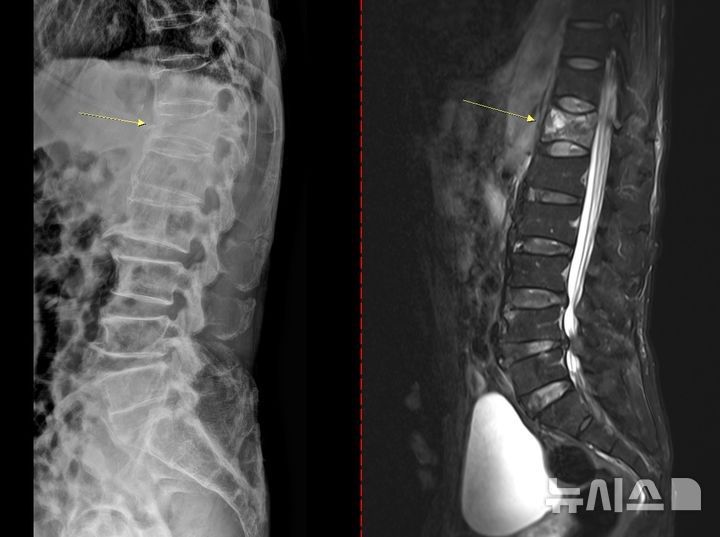

[서울=뉴시스] 골다공증성 압박골절 환자의 척추 엑스레이(왼쪽) 와 MRI(오른쪽). (사진= 고려대안산병원 제공)

골다공증은 초기 징후가 뚜렷하지 않아 특히 주의해야 한다. 통증이나 자각 증상이 거의 없다가 시간이 지나 가벼운 충격만으로도 손목이나 대퇴골(엉덩이뼈)이 골절되면서 뒤늦게 진단되는 경우도 있다. 때로는 등이 굽거나 키가 줄어드는 척추 압박골절이 나타날 수도 있다. 심할 경우 허리를 구부리거나 기침을 하는 등 일상생활 중에도 뼈가 쉽게 부러질 수 있다.

치료 없이 방치하면 뼈는 점점 약해지고 척추와 손목, 대퇴골 골절 등 중대한 골절이 발생할 수 있다. 특히 대퇴골 골절은 고령 환자에서 수술 후 합병증, 장기 입원, 사망률 증가와 직결되는 중증질환이다. 척추 압박골절의 경우 자세 변화, 만성 통증, 보행 장애를 유발해 ▲활동량 감소 ▲근력 저하 ▲추가 골절의 악순환으로 이어진다.